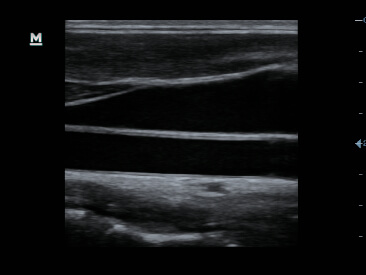

Gambar Klinis